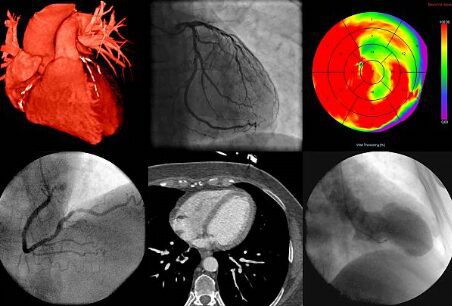

When it comes to diagnosing heart conditions, precision and reliability are key. At AMIS, we understand the importance of advanced diagnostic tools in healthcare. The Doppler test for the heart, also known as Doppler echocardiography, uses sound waves to evaluate the movement of blood through your heart and blood vessels. This non-invasive test provides vital information about the flow of blood, helping to diagnose various cardiac conditions. Stay with me as we delve deeper into how this technology could be pivotal in heart healthcare.

Doppler echocardiography is crucial because it offers a real-time picture of heart function without the need for invasive procedures. This test is particularly valuable for assessing heart valves and determining how well they work. It helps to detect problems like valve defects or blood flow issues within the heart which are critical in deciding the next steps for treatment.

A Doppler test can provide a wealth of information, including the speed and direction of blood flow through the heart’s chambers and valves. This is crucial for identifying conditions like heart valve stenosis or regurgitation (leaky valves), which can lead to serious heart complications if not addressed.